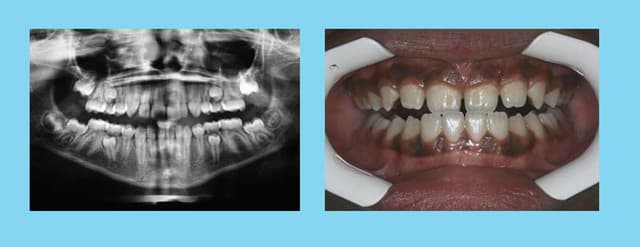

Dam. A.

Age :8 ans

Sexe M.

CL. III.

J’ai demandé à voir les parents, voici les dents du père !!!